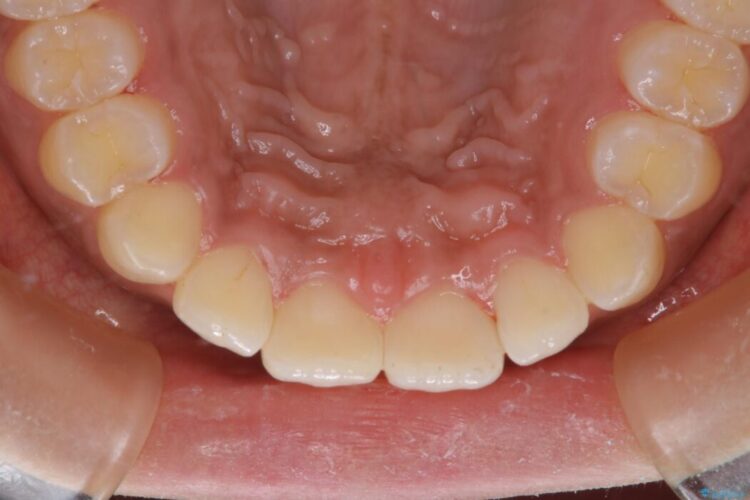

タバコによって付着したステインを綺麗にしたいとのことで来院されました。

ステインがこびりついていたため、PMTC60分コースを行いました。

タバコに含まれているタールが歯の黄ばみの原因になります。その黄ばみなどを、無理に落とそうとしたりすると歯の表面に傷がついてしまったり余計に汚れがつきやすい状態になることがあります。